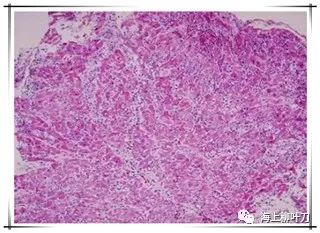

6.這是她的心肌病理切片,放大了100倍。

7.100倍還不是看得很清楚,放大400倍就很明顯了,一個(gè)個(gè)藍(lán)點(diǎn)就是淋巴球。這是很厲害的猛暴性心肌炎,整個(gè)心臟都被淋巴球浸潤(rùn)了。